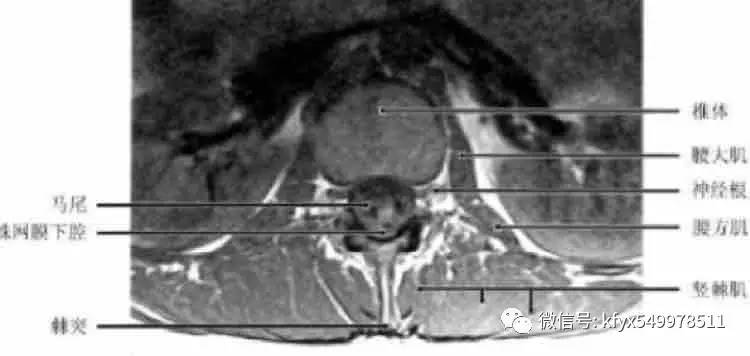

腰椎椎管由前面的椎体、侧面的椎弓、后面的椎板和棘突组成。在上腰椎段椎管横断面为圆形或卵圆形,在中段或下段腰椎椎管横断面呈三角形,横径等于或大于前后径。腰椎管的侧隐窝为椎间孔内口,它位于椎弓根的内侧和上关节突的前方,椎体的后外侧和相近的椎间盘构成侧隐窝的前壁。

椎间孔的界线是:①上下方为椎弓根;②外侧为椎体的后外方;③前内侧为椎间盘;④后外侧为上关节突。

在SE序列横轴及矢状方位T1加权像上,神经根表现为贴近椎弓根的硬膜外脂肪围绕的低信号。

(3)椎管内结构:①硬膜外间隙:硬膜外间隙系骨性椎管与硬脊膜之间的空隙,其内主要含脊神经、动脉、静脉、脂肪及少量结缔组织。腰椎的硬膜外间隙填充相当厚的硬膜外脂肪、韧带、神经和血管。硬膜外脂肪在T1及T2加权像上呈高信号强度。硬脊膜为致密纤维组织,在神经根平面外突,其内含有蛛网膜,共同构成神经根鞘。蛛网膜位于硬脊膜内面,二者之间有潜在的硬膜下隙。在MRI下,硬脊膜难与蛛网膜区分开,二者统称为鞘膜。②蛛网膜下隙:脊髓表面包绕软脊膜,软脊膜与蛛网膜之间为蛛网膜下隙。在MRI图像上见到的鞘膜囊内的脑脊液,实际是位于蛛网膜下隙的,脑脊液在T1加权图像上为低信号。在T2加权图像上信号高于脊髓。蛛网膜下隙在L2以下比较宽,由脑脊液填充,在T1加权像呈低信号强度,在L2加权像呈高信号强度,明显高于脊髓,因而脊髓结构可清晰显示。③脊髓马尾:脊髓位于蛛网膜下隙的中央.其末端为圆锥,圆锥的末端可在矢状面图像上清楚显示,止于L1,2平面。在T1加权像呈中等信号强度,在T2加权像信号强度比椎间盘和脑脊液低,为此二者易区分。脊髓的灰质与白质的MRI信号亦有不同,在横断面T1加权图像上,中央灰质是H形高信号,而周围白质信号较低。脊髓圆锥向下移行为纤维性终丝。终丝的信号强度类似或低于脊髓信号。约5%的正常人终丝内含有不同量的脂肪,信号明显增高。在圆锥平面向下走行的腰骶神经根称作马尾。马尾神经由上至下逐渐变少。旁正中矢状位显示神经根呈扇形从后上向前下方向延伸。④神经根的信号强度较低,但在脂肪组织的衬托下仍然十分清楚。静脉及静脉丛仍为低信号。大部分韧带为胶原纤维组织,在T1、T2加权图像上及部分翻转梯度回波图像上为低信号,黄韧带内含大量弹性纤维,故在T1 、T2加权图像上为中等强度信号。